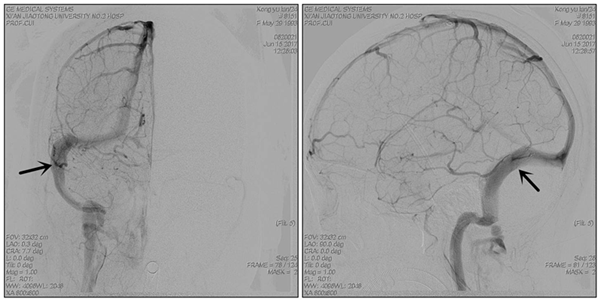

术后造影显示静脉窦狭窄消失

经过5天的术前抗血小板治疗,于2017年6月10日成功为患者施行了静脉窦狭窄支架成形术,术中顺利,即刻测量狭窄远、近端压力差为:0。术后患者头痛完全缓解,视力也开始慢慢恢复、癫痫发作完全消失,3日后腰穿颅内压下降为75mmH2O,转当地医院眼科继续治疗。